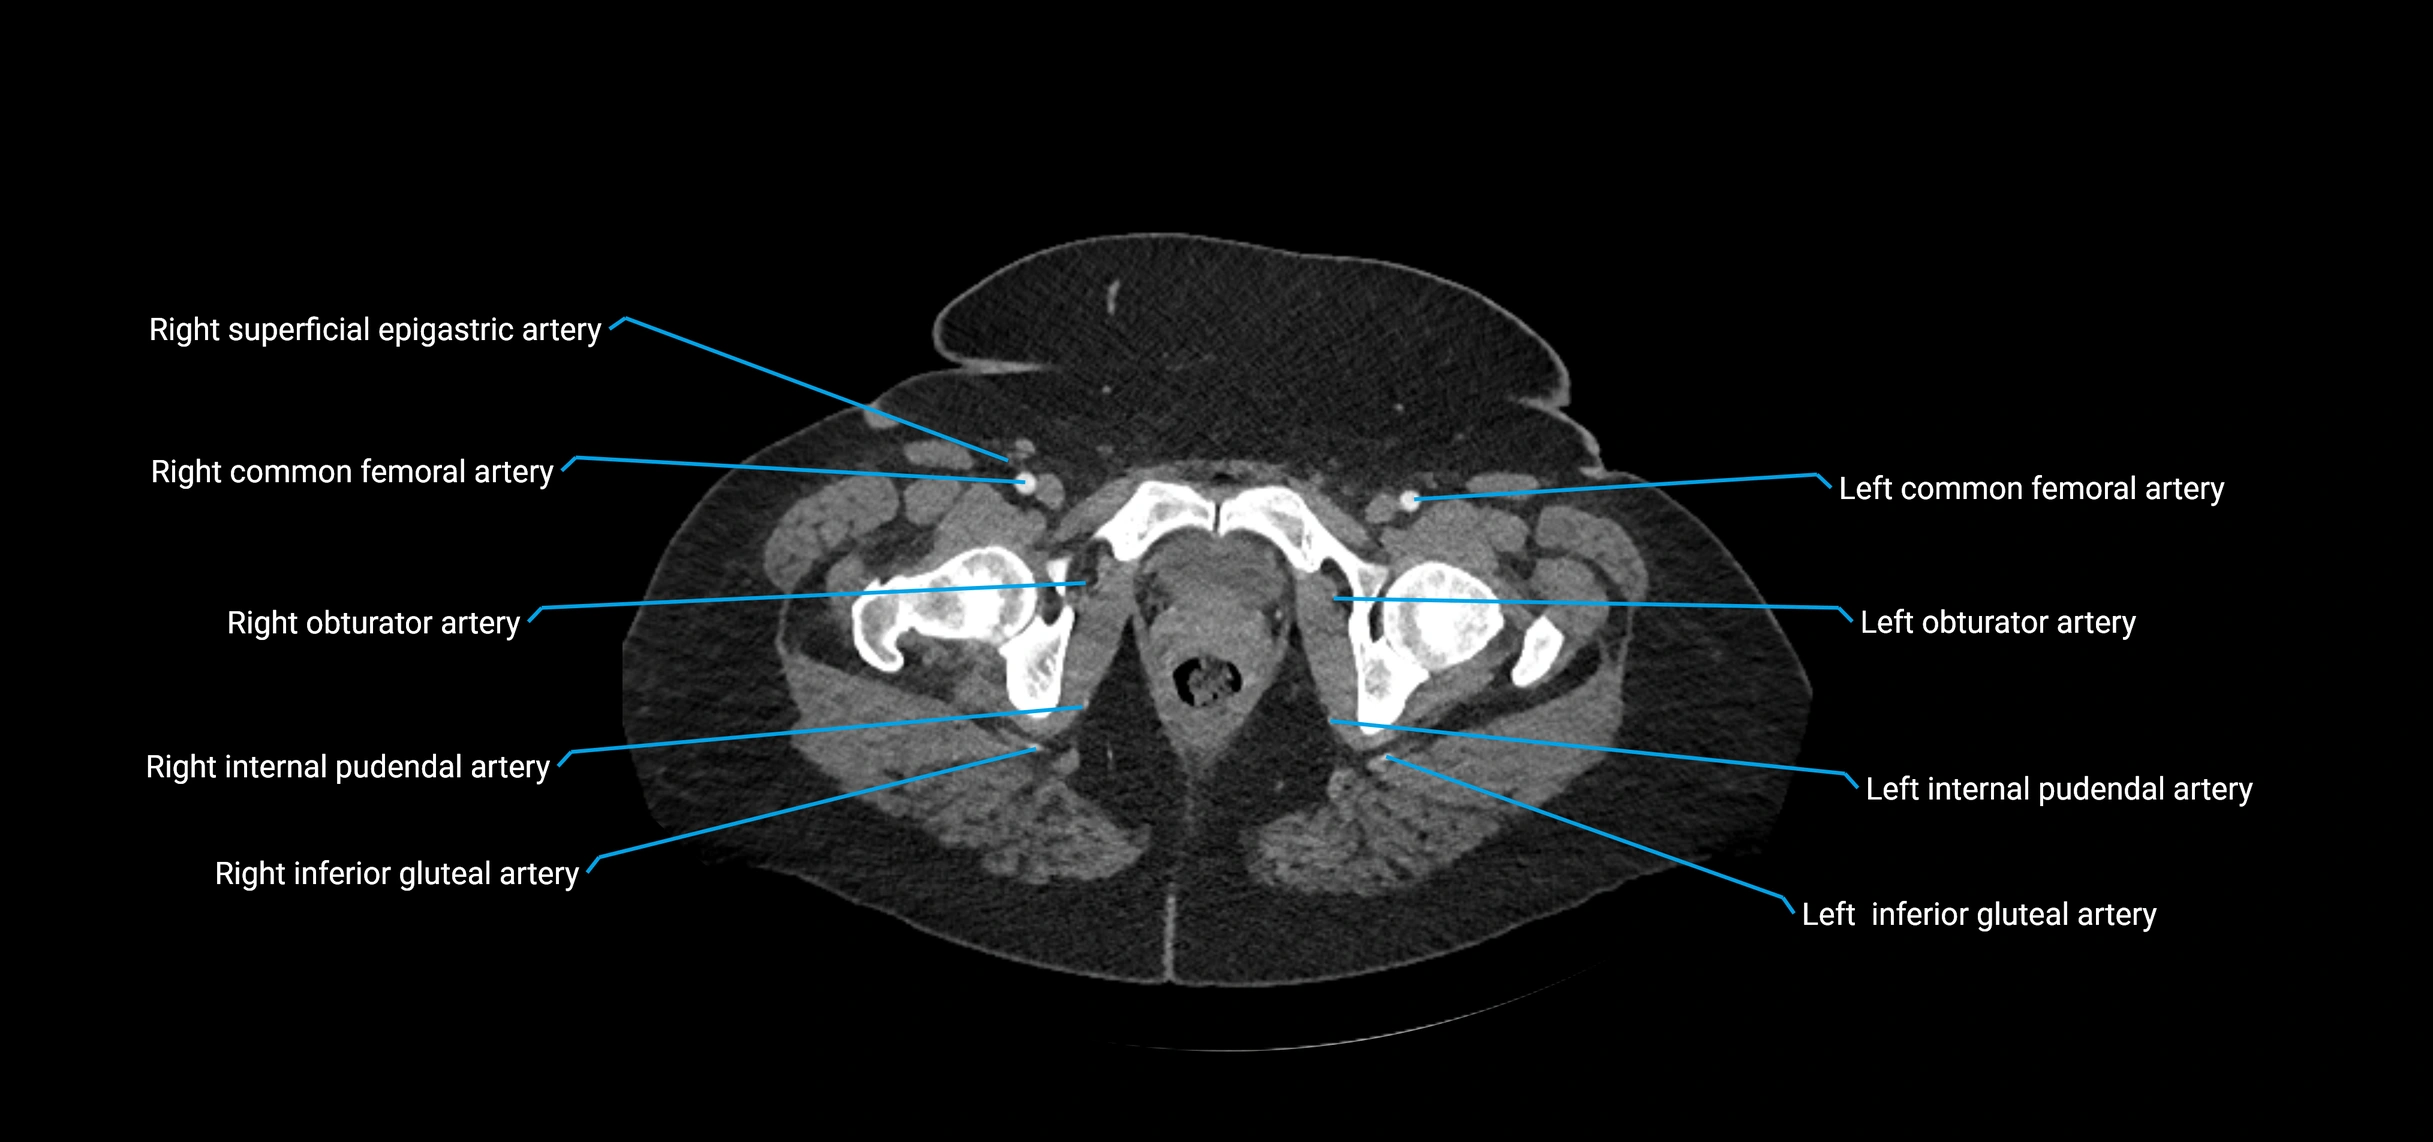

CT images

image

Contrast-enhanced CT (CTA):

• Gold standard for abdominal aortic imaging

• Provides excellent detail of lumen, wall, aneurysm, thrombus, and branch vessels

• Multiplanar and 3D reconstructions help in aneurysm measurement, stent graft planning, and dissection evaluation